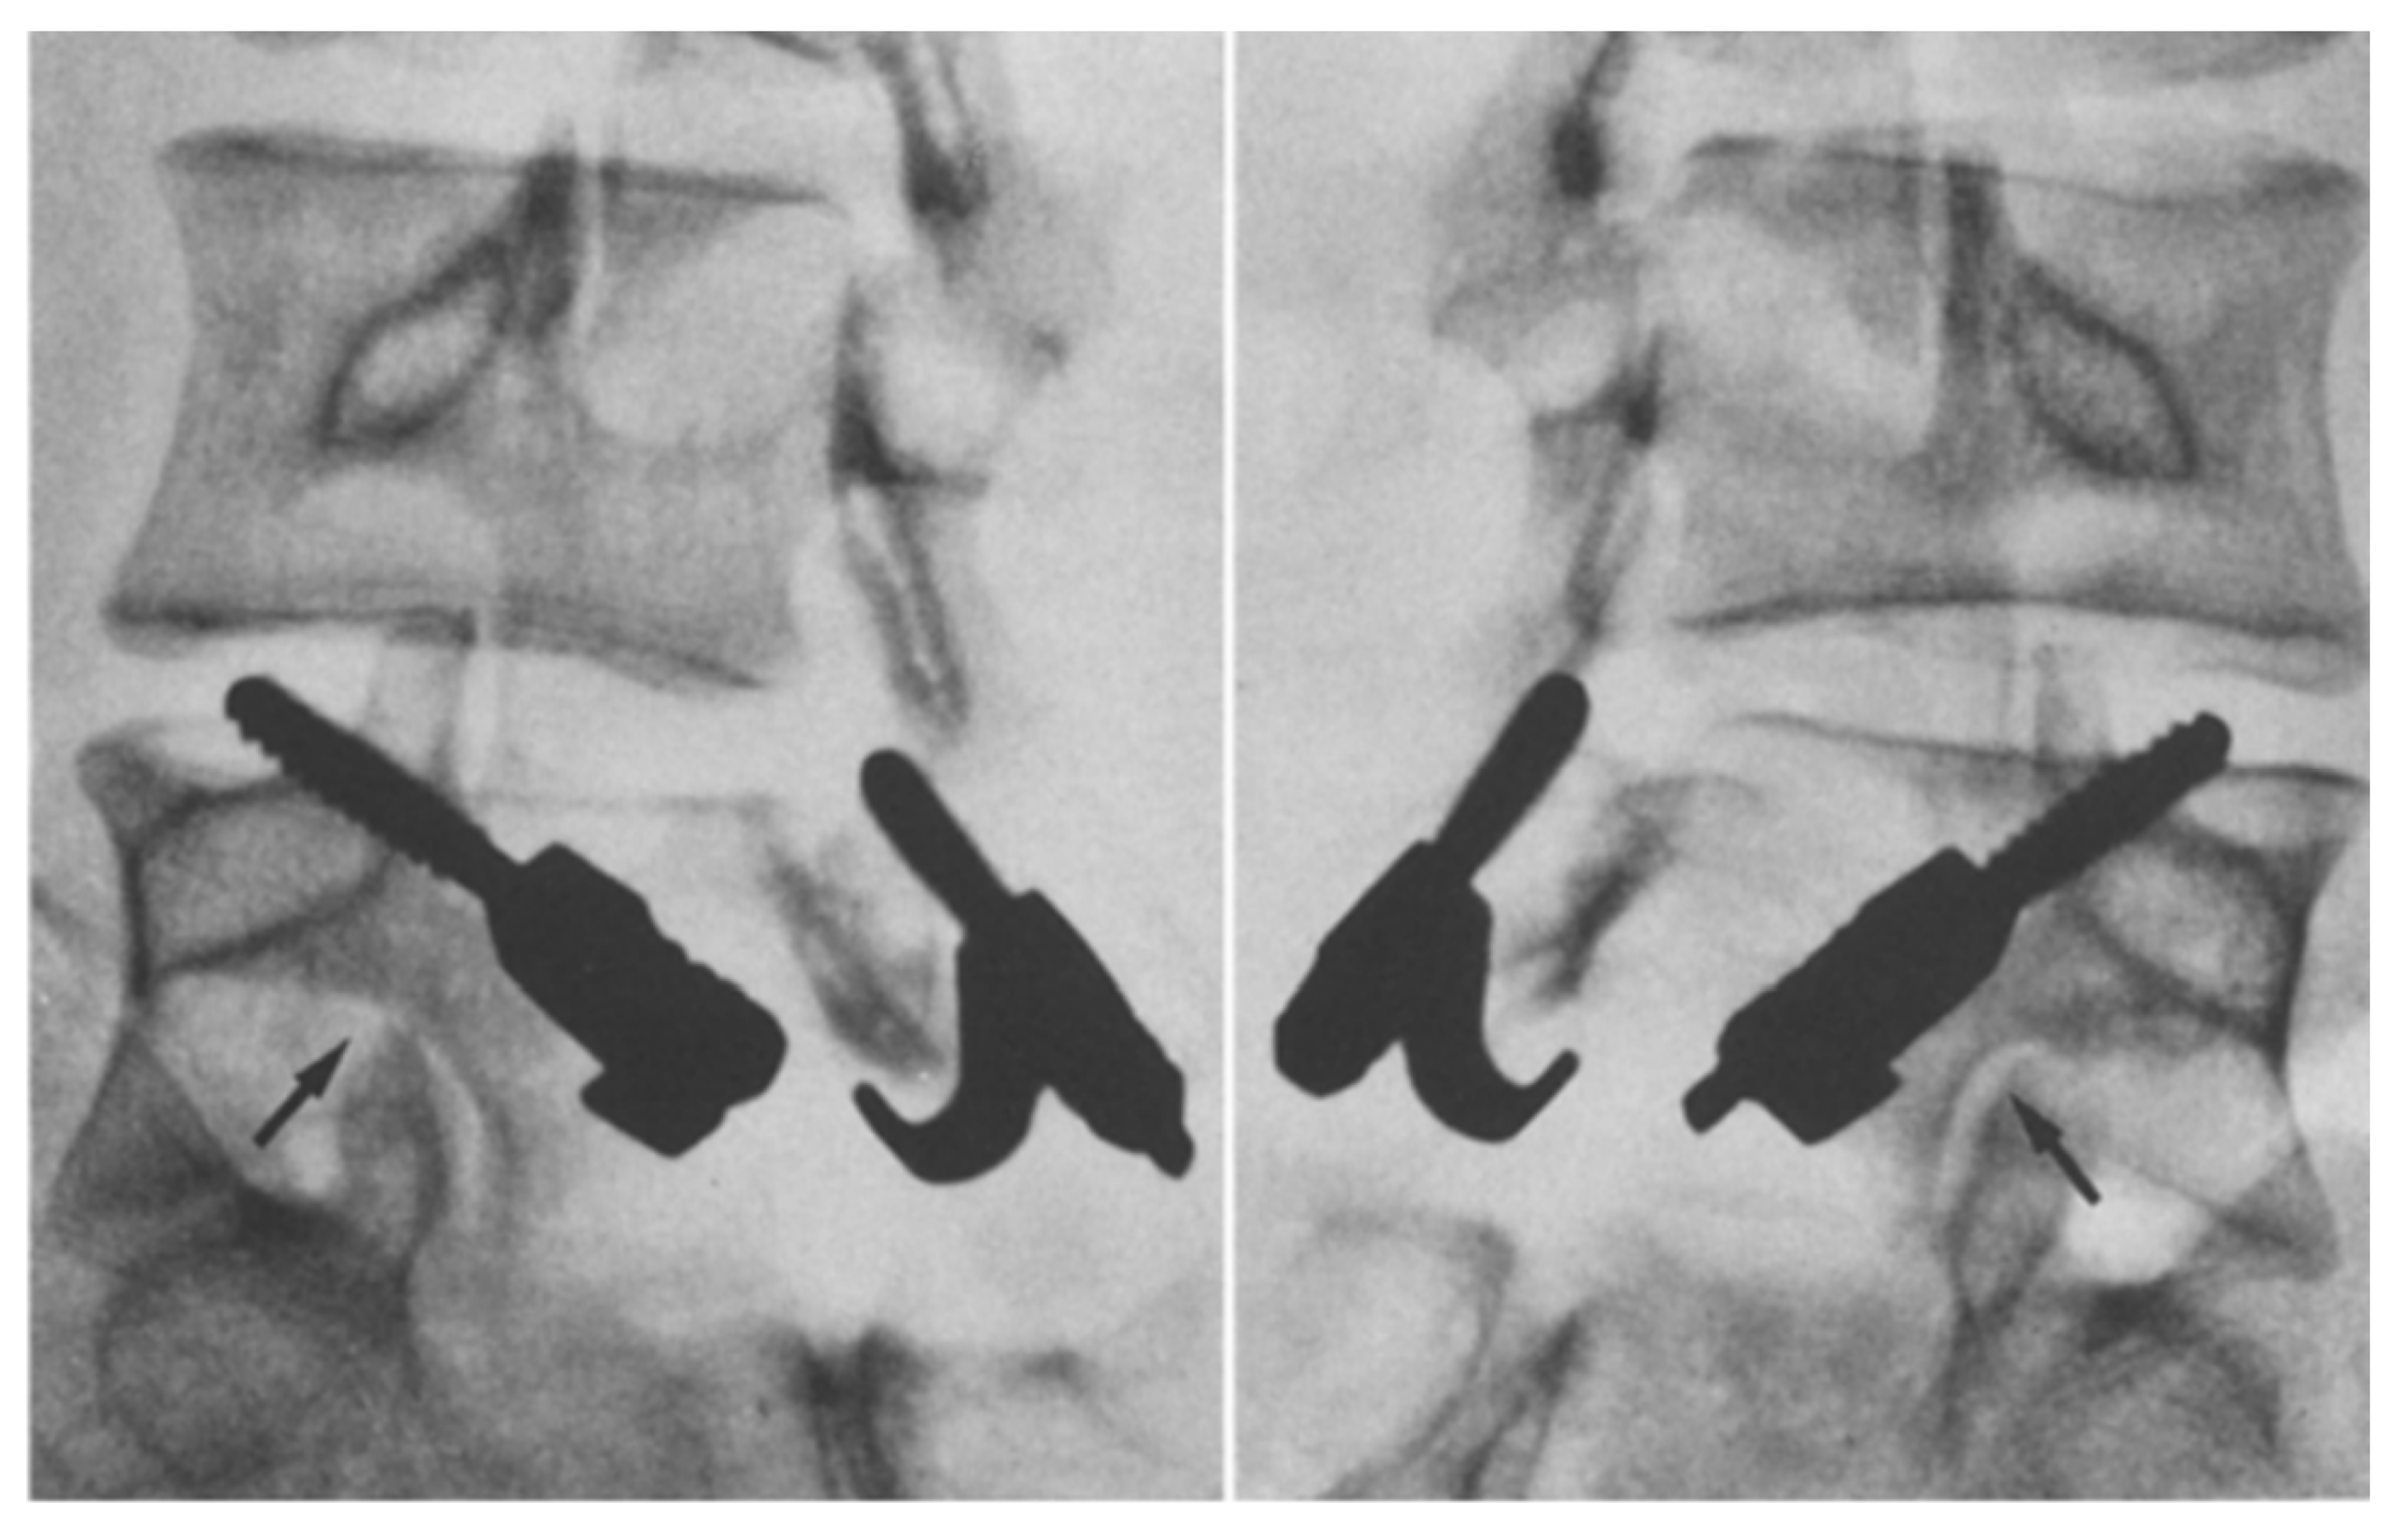

1.9.1. Buck’s Repair

- Buck, J.E. Direct repair of the defect in spondylolisthesis. J. Bone Jt. Surg. Br. Vol. 1970, 52-B, 432–437. [Google Scholar] [CrossRef]

- Li, Y.; Li, H.; Chang, X.; Hu, Z.; Mu, X.; Liu, C.; Gao, X.; Zhang, Y.; Zhou, Y.; Li, C. Retrospective comparative study of pedicle screw fixation via quadrant retractor and buck’s technique in the treatment of adolescent spondylolysis. Orthop. Surg. 2022, 14, 111–118. [Google Scholar] [CrossRef] [PubMed]

- Bonnici, A.V.; Koka, S.R.; Richards, D.J. Results of Buck screw fusion in grade I spondylolisthesis. J. R. Soc. Med. 1991, 84, 270–273. [Google Scholar] [CrossRef]

- Snyder, L.A.; Shufflebarger, H.; O’Brien, M.F.; Thind, H.; Theodore, N.; Kakarla, U.K. Spondylolysis outcomes in adolescents after direct screw repair of the pars interarticularis. J. Neurosurg. Spine 2014, 21, 329–333. [Google Scholar] [CrossRef]